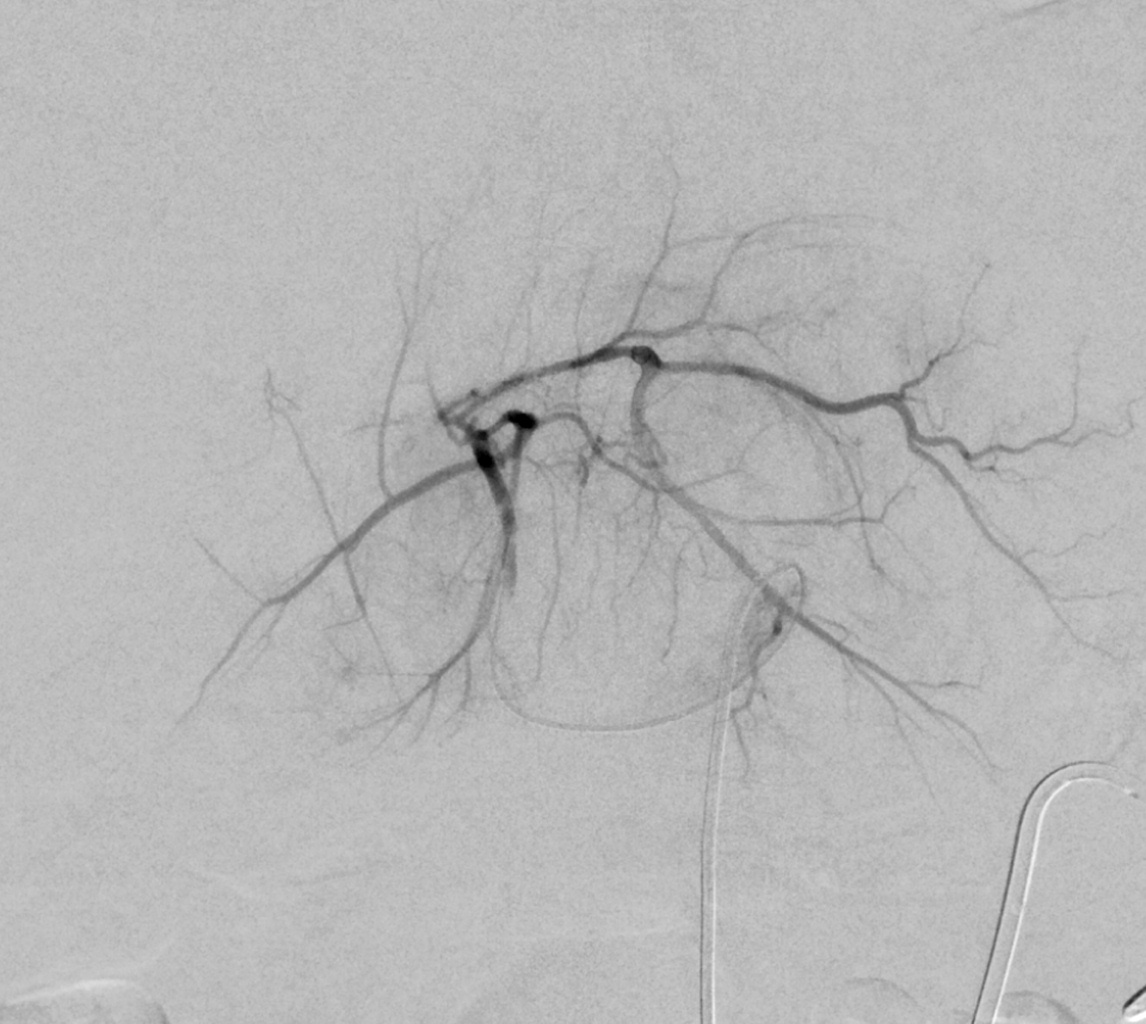

Der Tumor wird selektiv mit einem Mikrokatheter ausgesucht und lokal chemoperfundiert.

Mittels moderner intraoperativer Bildgebung wird sichergestellt, dass ausschliesslich der Tumor behandelt wird. So werden Komplikationen vermieden.